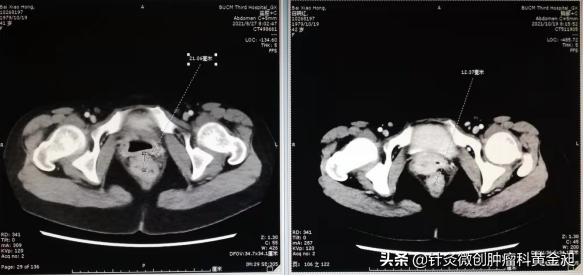

以下是患者治疗前后肛周肿物的对比图以及化疗前后的影像学对比图: